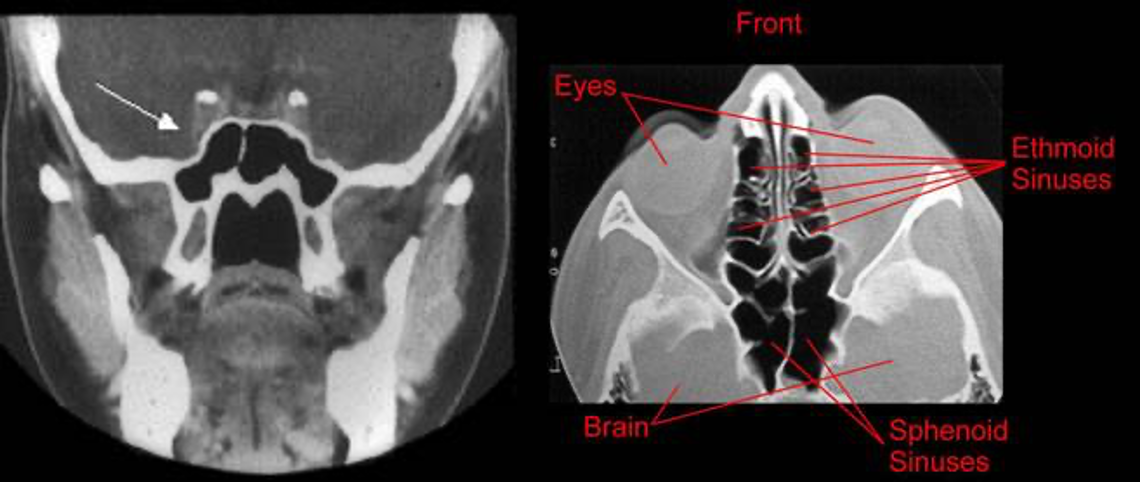

The Ethmoid Sinuses

- Anterior ethmoids: drain into the middle meatus

- Posterior ethmoids: drain into superior meatus

The Sphenoid Sinus